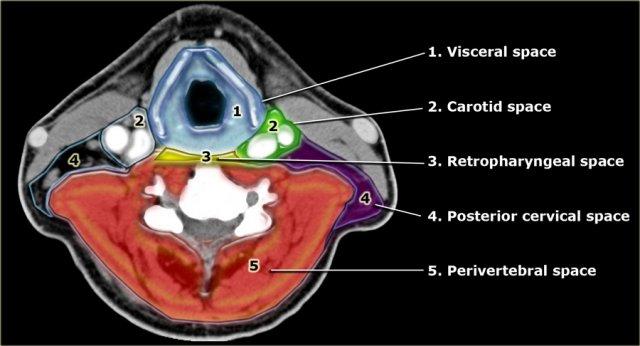

Các khoang của vùng cổ dưới móng

- Khoang tạng

Ngăn trung tâm chứa nhiều tạng như thanh quản, tuyến giáp, hạ họng và thực quản cổ. - Khoang cảnh

Khoang đôi nằm ngay bên ngoài ngăn tạng, chứa động mạch cảnh trong, tĩnh mạch cảnh trong và một số cấu trúc thần kinh. - Khoang sau hầu

Khoang ảo nhỏ chỉ chứa mô mỡ, liên tục với khoang trên móng và trung thất giữa. - Khoang cổ sau

Khoang đôi nằm sau bên so với khoang cảnh.

Chứa mô mỡ, hạch bạch huyết và các thành phần thần kinh. - Khoang cạnh sống

Khoang lớn này bao quanh hoàn toàn thân đốt sống, bao gồm các cơ trước và cạnh sống.